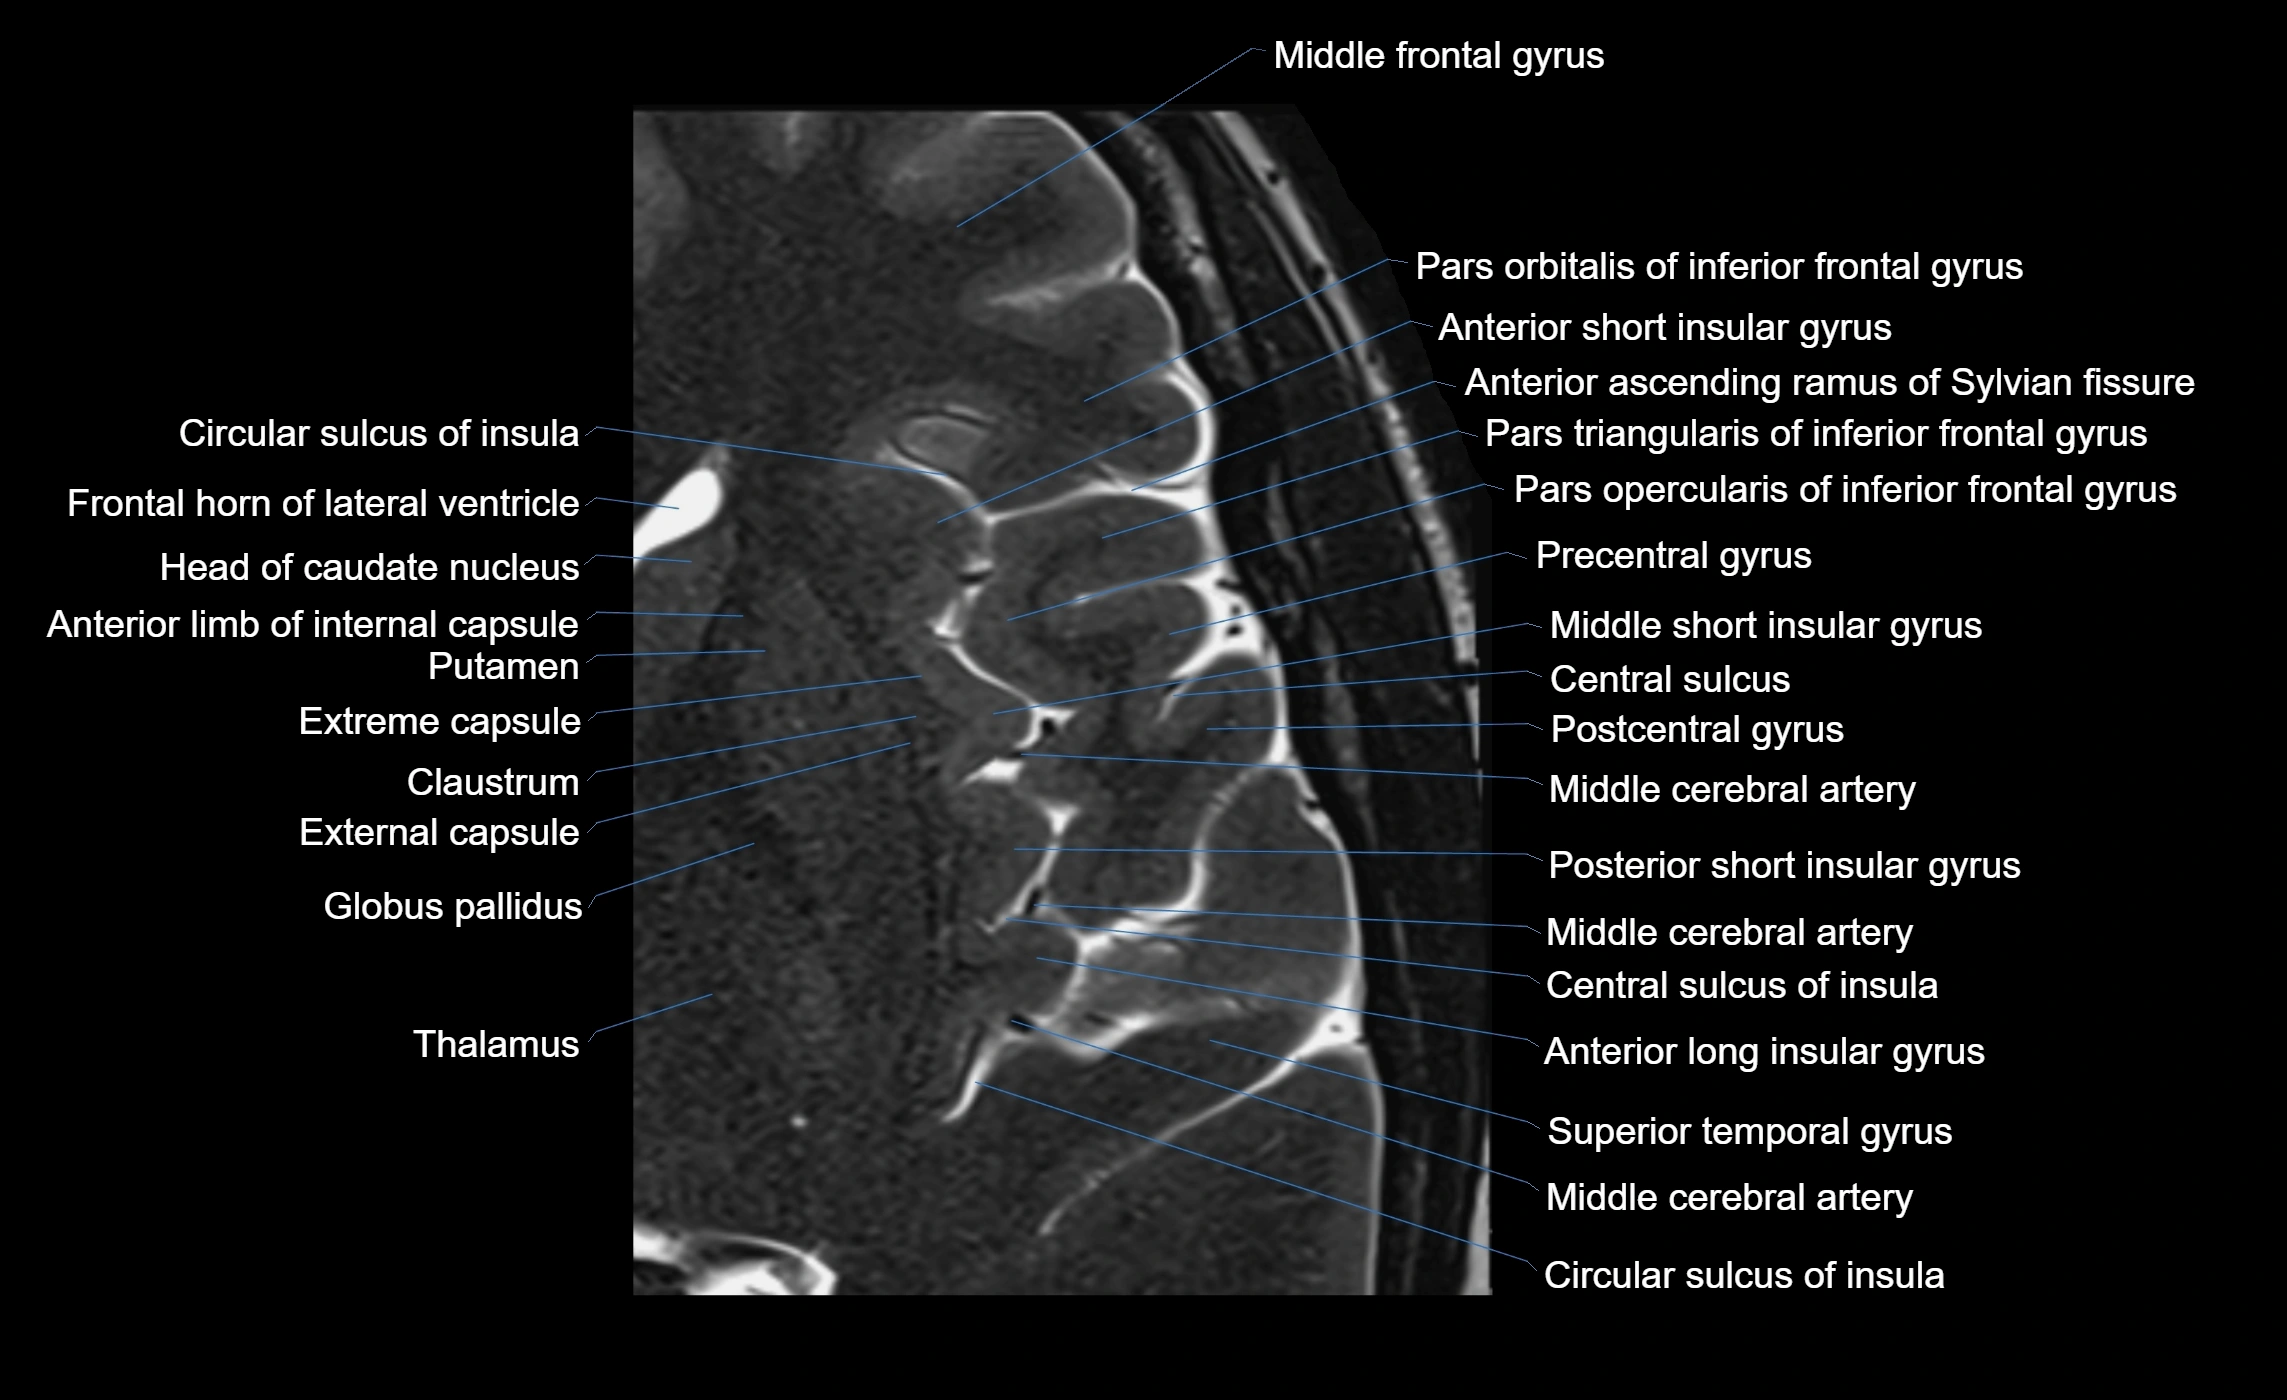

The anterior ascending ramus of the Sylvian fissure is a significant anatomical landmark in the lateral surface of the cerebral hemisphere. It represents one of the key branches of the Sylvian fissure (also known as the lateral sulcus) and plays an essential role in demarcating the boundaries between important cortical regions, notably within the frontal and parietal lobes. Understanding its anatomy and imaging appearance is crucial in neuroradiology, neurosurgery, and neuroanatomy for accurate localization and identification of adjacent brain structures.

• The anterior ascending ramus is a short, superiorly oriented branch that arises from the main stem of the Sylvian fissure.

• It projects upward (anteriorly and slightly dorsally) from the lateral sulcus into the inferior frontal gyrus.

• This ramus separates the pars opercularis (opercular part) from the pars triangularis (triangular part) of the inferior frontal gyrus.

• The anterior ascending ramus marks the boundary between Broca's area and adjacent cortical areas in the dominant hemisphere.

• T1-weighted imaging:

• The Sylvian fissure and its anterior ascending ramus appear as low-signal intensity (dark) CSF-filled clefts between the gyri.

• Clear demarcation between adjacent gray and white matter.

• T2-weighted imaging:

• The fissure, including the anterior ascending ramus, is hyperintense (bright) due to CSF signal.

• Better visualization of the separation between opercular and triangular parts of the inferior frontal gyrus.